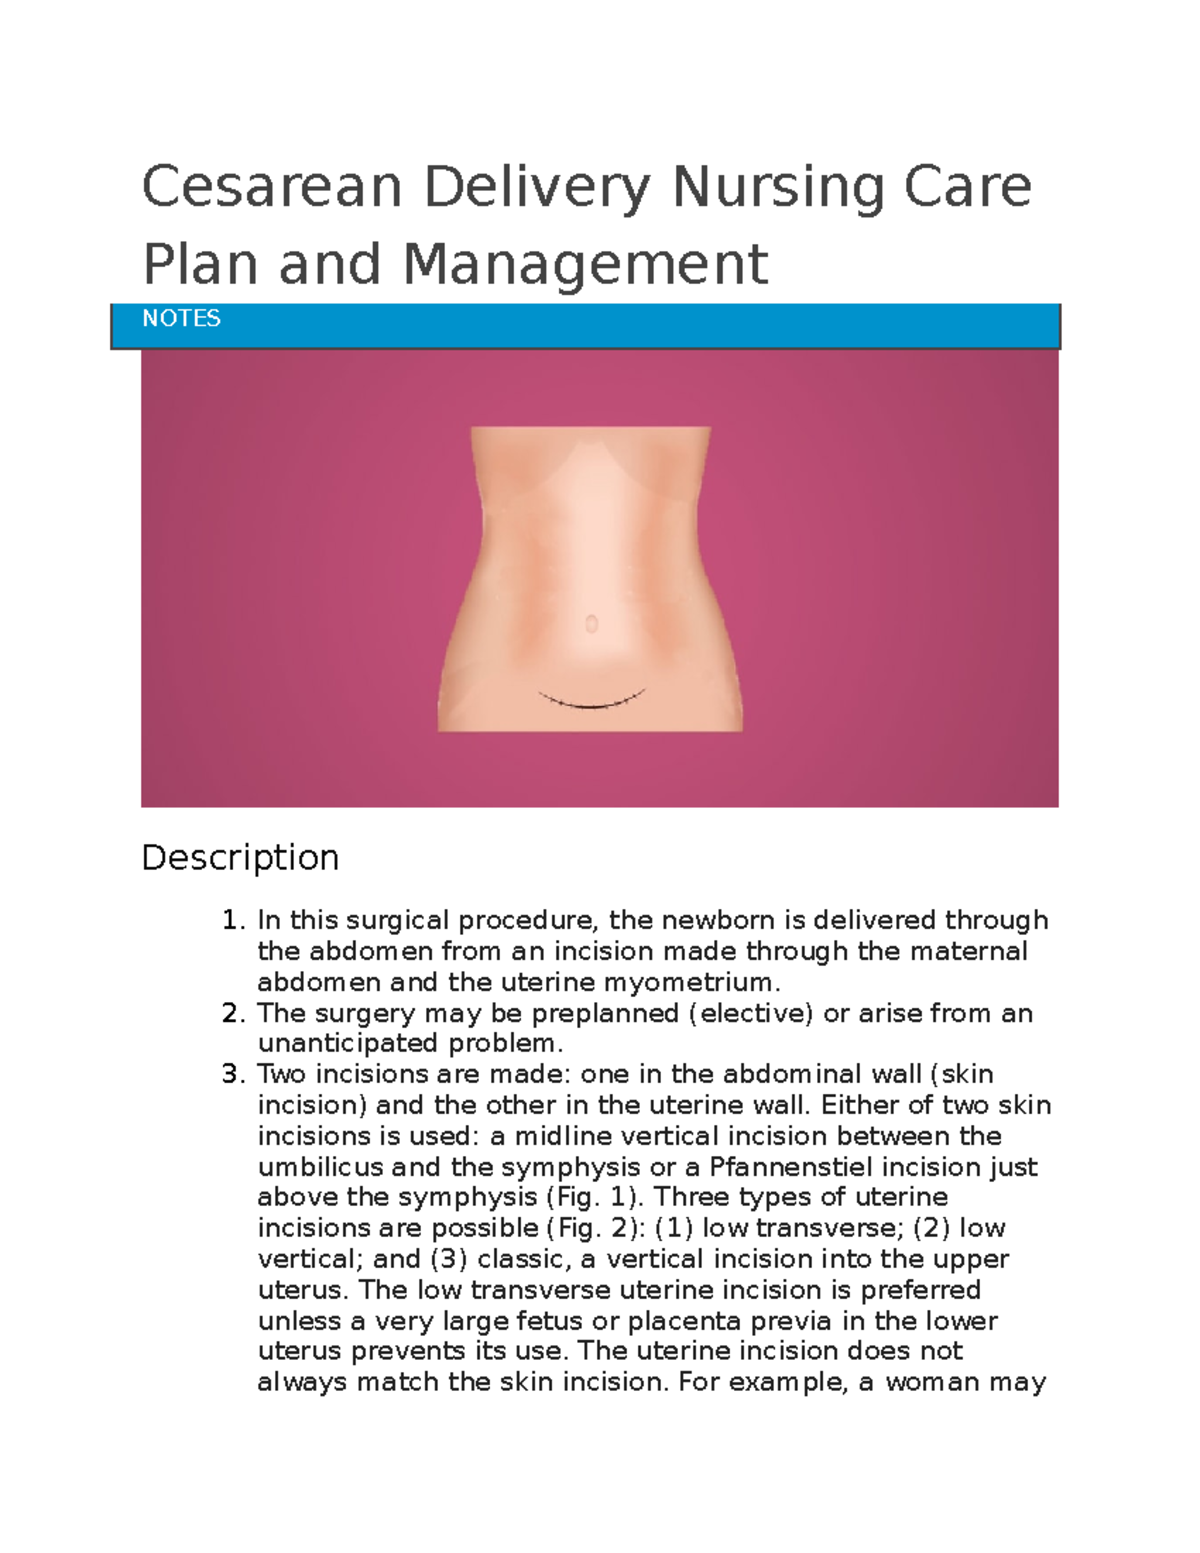

Cesarean Delivery Nursing Care Plan And Management Cesarean Delivery